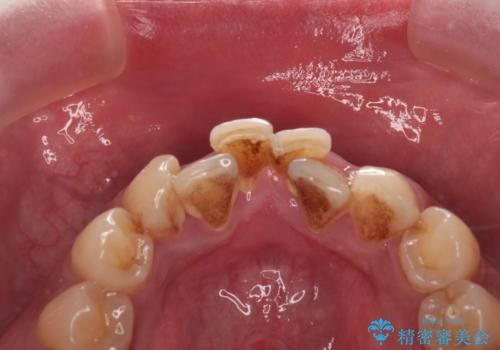

コーヒー、タバコなどで着色した歯をPMTCで、きれいに!!

- 長年の喫煙とコーヒーによる歯の、着色をとりたいと来院されました。

かなり汚れがこびりついていたので、PMTC(歯科医院で行うプロフェッショナルクリーニング)60分コースを

おすすめしました。

歯の着色だけでなく、汚れもとれ歯の表面がツルツルなって気持ちがいいと

大変満足していただけました。